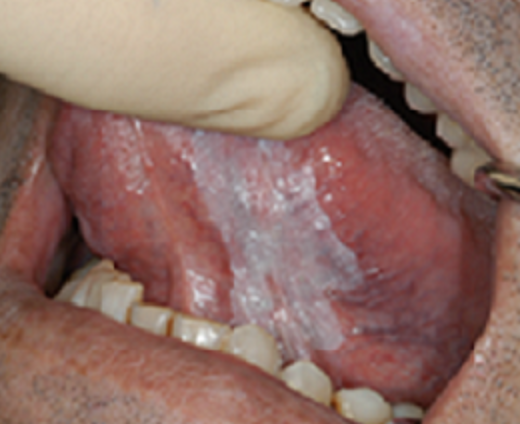

Q

What should you do about this?

(present for 2 weeks)

A

Advise referral to an oral maxillofacial surgeon for excision of the lesion to send for histopathology

what is this and what do you do?

This in particular is oral leukoplakia which is just a term for a non removable white lesion.

It can be homogenous like that picture or not (irregular, patchy and colour variation)

Because it can be an SCC or SCC in situ, this needs referral for biopsy